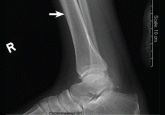

ArticleJoint pain in a man with lung cancer Author:Nadia Siddiqi, DOPublish date: January 1, 2015Hypertrophic pulmonary osteoarthropathy is characterized by proliferation of the skin and periosteal formation of new bone.Read More